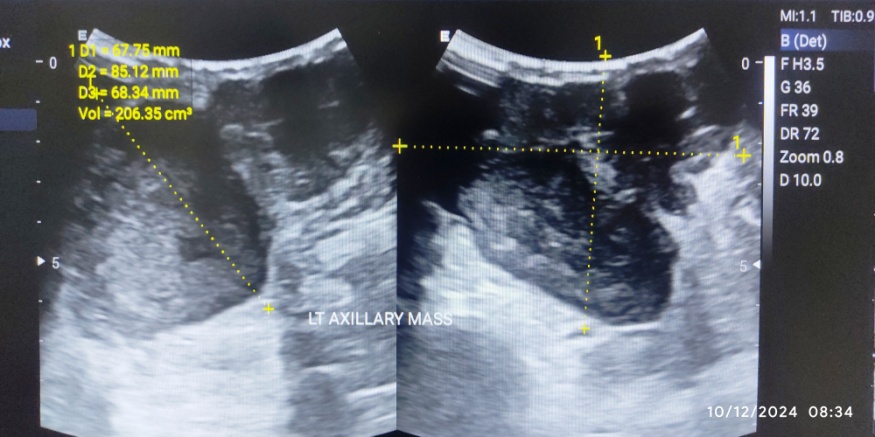

A 40 y old female presented with a palpable mass at the left axilla, which had been present for a month with rapid growth. Breast ultrasound showed a huge mass with lobulated borders and internal cystic clefts at the left axilla with an approximate size of 10.0 x 9.0 x 9.0 cm (fig. 1).

Fig. 1: Ultrasonography image showing huge mass with lobulated borders and internal cystic clefts with an approximate size of 10.0 x 9.0 x 9.0 cm at the left axilla